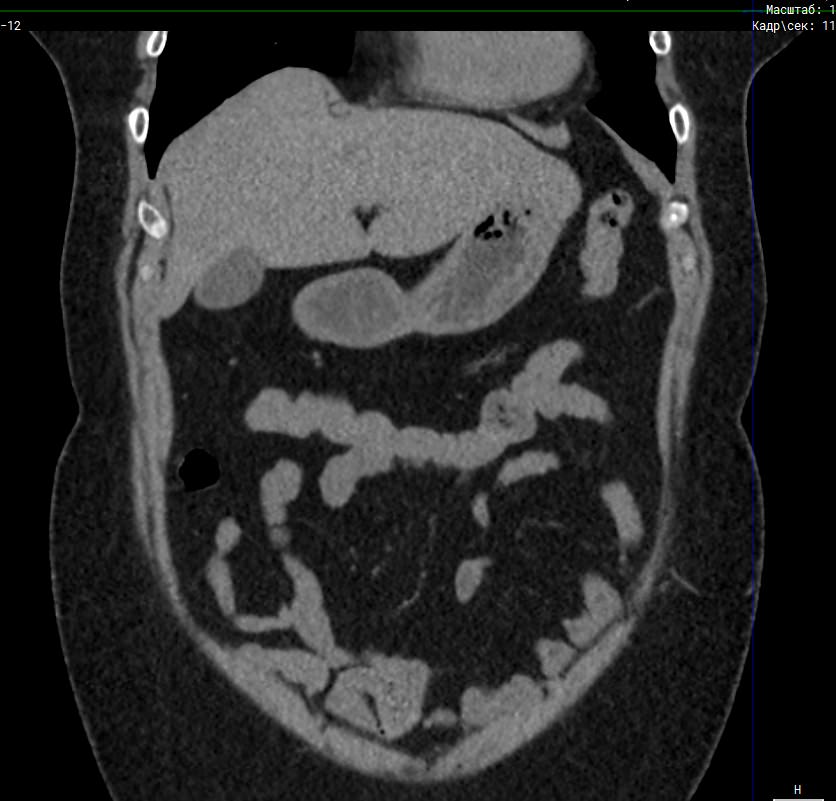

Мультиспиральная компьютерная томография (МСКТ) брюшной полости относится к современным лучевым методам исследования, с помощью которого можно оценить состояние органов брюшной полости (печени, желчного пузыря, поджелудочной железы, селезенки), прилегающих к ним кровеносных сосудов и лимфатических узлов.

С помощью мультиспиральной компьютерной томографии проводятся послойные рентгеновские снимки исследуемой области с толщиной среза от 0,5 мм. В нашей клинике исследование выполняется на компьютерном томографе экспертного класса TOSHIBA AQUILION CXL, который оснащен 128 детекторами, позволяющими получать за несколько секунд снимки брюшной полости с высокой точностью. Большое количество детекторов позволяет получить точные данные, при этом сократить время исследования и сделать минимальной лучевую нагрузку на пациента. Кроме того, инновационные технологии аппарата дают возможность сформировать объемную модель органа и окружающих структур, что также способствует проведению точной и достоверной диагностики.

При подозрении на опухоли, воспалительные процессы, гнойные очаги назначается КТ брюшной полости с внутривенным болюсным контрастированием. Для этого пациенту внутривенно вводится рентгеноконтрастное вещество на основе йода. Благодаря усиленному кровоснабжению препарат накапливается в структуре патологических образований и помогает врачу-рентгенологу выявить изменения в структуре внутренних органов.

Метод контрастирования помогает максимально точно выявить очаг патологии уже на начальной стадии, а также установить его локализацию, точные размеры, форму и особенности кровоснабжения.